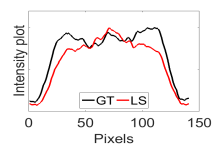

The calculated correlation coefficient (), SNR, as well as CNR values for all tested methods in the synthetic phantom experiment are shown in Table II. As seen in Table II, the proposed NCBC method achieved the highest , CNR as well as SNR values when compared to that of other tested methods. Visual results from the bias-corrected DW-MR synthetic phantom data produced using different tested methods is shown in Fig. 2(c-i). It can be observed that the MCBC, LEMS, and proposed NCBC method were able to achieve the best level of bias correction when compared to the other tested methods. This is particularly apparent in the peripheral zone (PZ) of the prostate gland as highlighted using red ROIs in Fig. 2(a-i), where intensity inhomogeneities are still present to a significant degree in the bias-corrected phantom data produced using the LS, SCIC, SGD and BCFCM methods, while strong inhomogeneity correction performance is achieved using MCBC, LEMS, and the proposed NCBC method. Furthermore, it can be observed that NCBC exhibited minimal intensity inhomogeneities when compared with MCBC and LEMS, particularly in the area that is highlighted using Red ROIs. To better represent the outperforming of proposed NCBC method in terms of bias correction using synthetic phantom, the data intensity profiles corresponding to the drawn blue line in Fig. 3(a) are shown in Fig. 3(b) for uncorrected data (red color plot) versus ground truth data (black color plot) and in Fig. 3(c-i) for corrected data using different tested methods (red color plots) versus ground truth data (black color plots). As the intensity profiles of Fig. 3(b-i) show, NCBC method was resulted in an intensity profile with the most flatness and less amount of variation compared to the intensity profiles of uncorrected image as well as reconstructed images using other tested methods as such confirms the better performance of proposed NCBC method in terms of bias field correction.